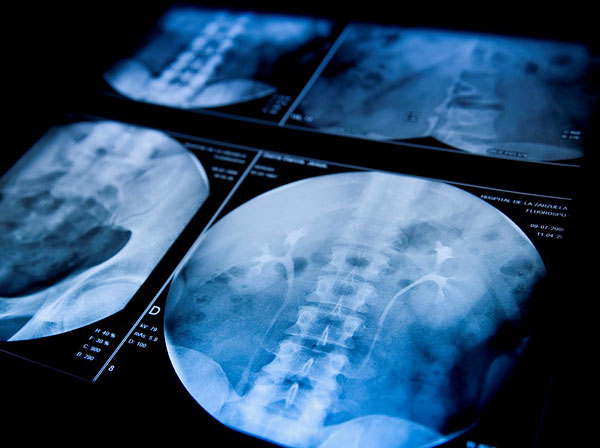

腹部超音波檢查,可明顯看到結(jié)石陰影,是最有效的確診工具。一旦曾有癥狀,未來(lái)再發(fā)作的機(jī)會(huì),則會(huì)高達(dá)三○%左右。若是已有癥狀或發(fā)現(xiàn)膽囊已經(jīng)發(fā)炎、變厚或是塞滿結(jié)石,有如不定時(shí)炸彈,也已經(jīng)失去儲(chǔ)存膽汁的功能,要慎重考慮摘除膽囊。?